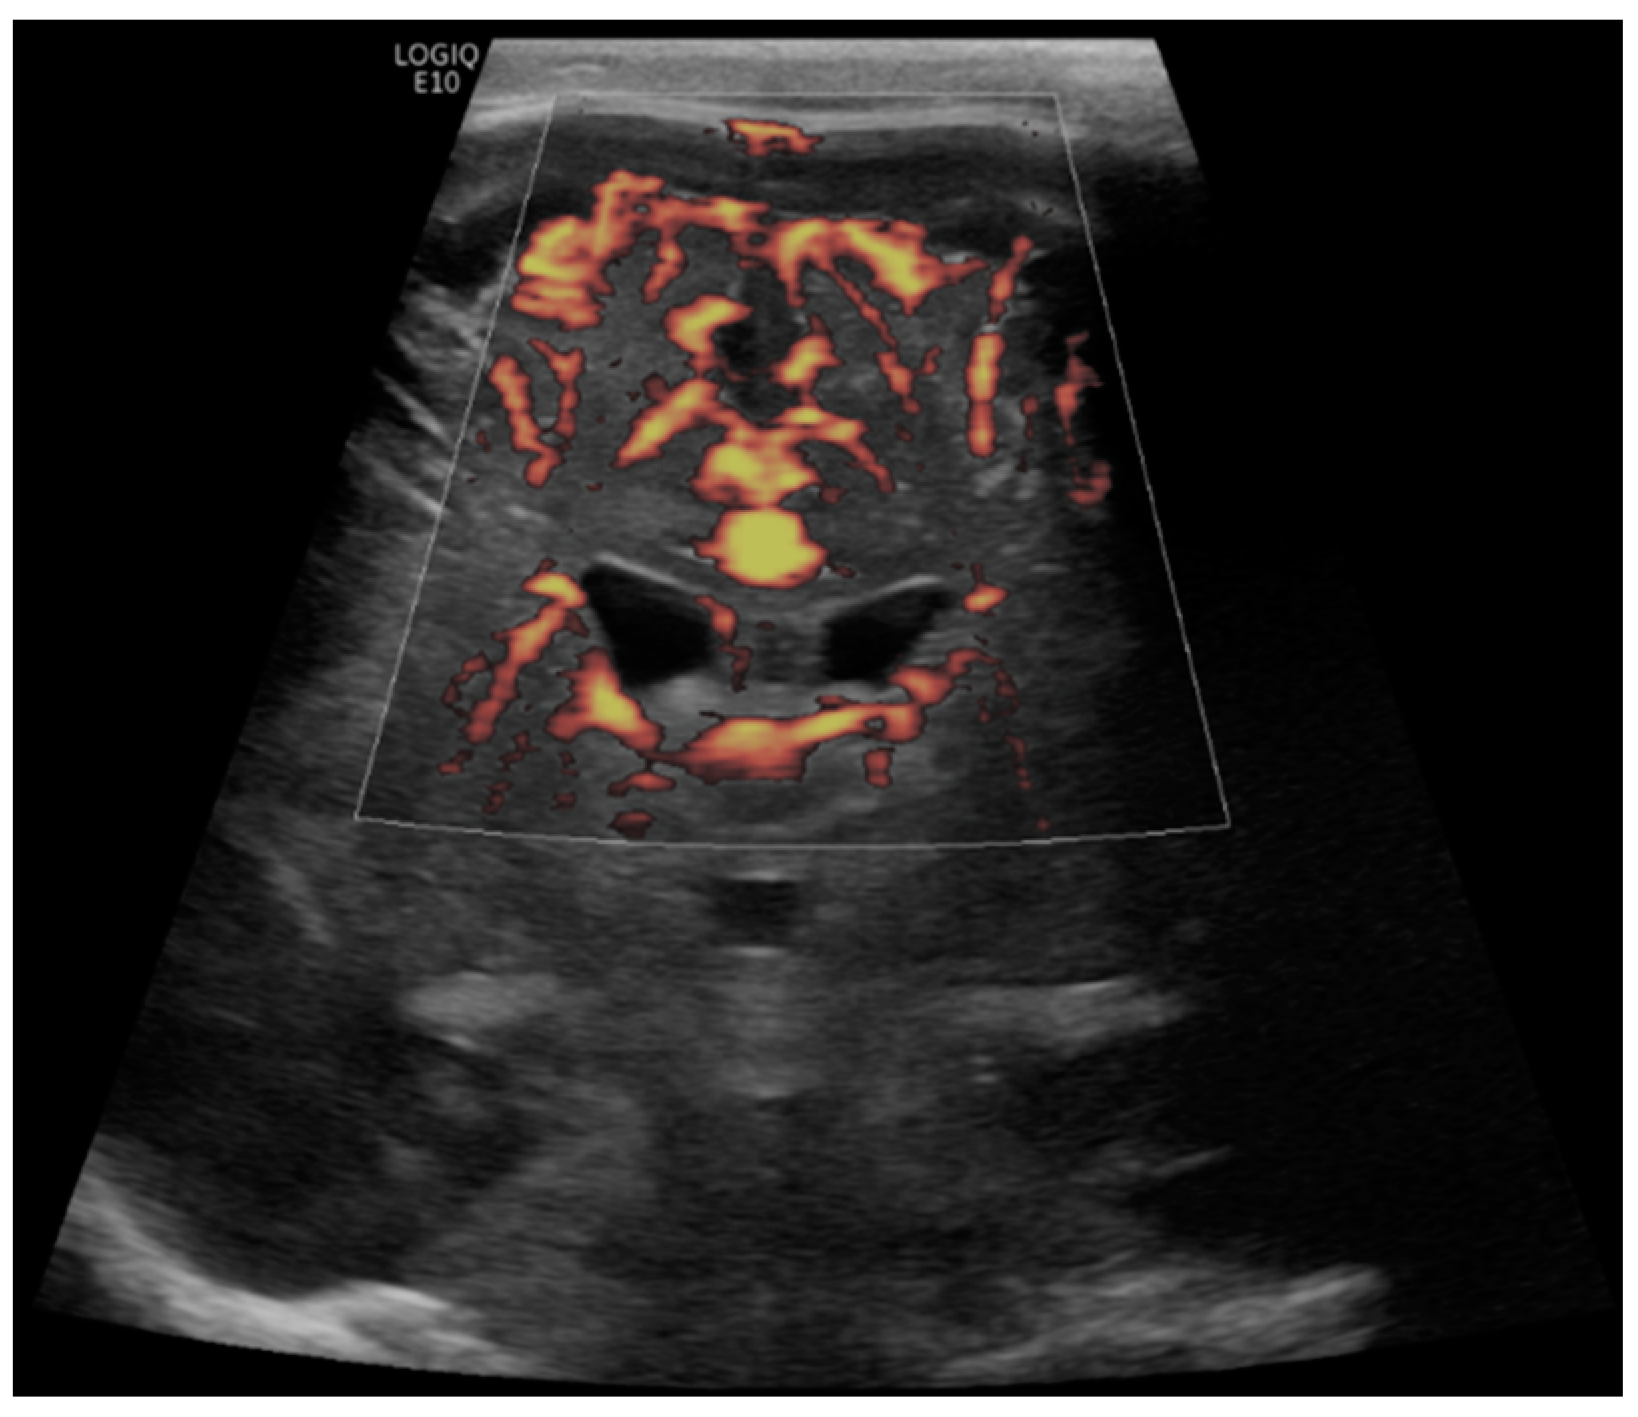

- Hwang, M.; Haddad, S.; Tierradentro-Garcia, L.O.; Alves, C.A.; Taylor, G.A.; Darge, K. Current understanding and future potential applications of cerebral microvascular imaging in infants. Br. J. Radiol. 2022, 95, 20211051. [Google Scholar] [CrossRef] [PubMed]

- Barletta, A.; Balbi, M.; Surace, A.; Caroli, A.; Radaelli, S.; Musto, F.; Saruggia, M.; Mangili, G.; Gerevini, S.; Sironi, S. Cerebral superb microvascular imaging in preterm neonates: In vivo evaluation of thalamic, striatal, and extrastriatal angioarchitecture. Neuroradiology 2021, 63, 1103–1112. [Google Scholar] [CrossRef]

- Goeral, K.; Hojreh, A.; Kasprian, G.; Klebermass-Schrehof, K.; Weber, M.; Mitter, C.; Berger, A.; Prayer, D.; Brugger, P.C.; Vergesslich-Rothschild, K.; et al. Microvessel ultrasound of neonatal brain parenchyma: Feasibility, reproducibility, and normal imaging features by superb microvascular imaging (SMI). Eur. Radiol. 2019, 29, 2127–2136. [Google Scholar] [CrossRef] [PubMed]